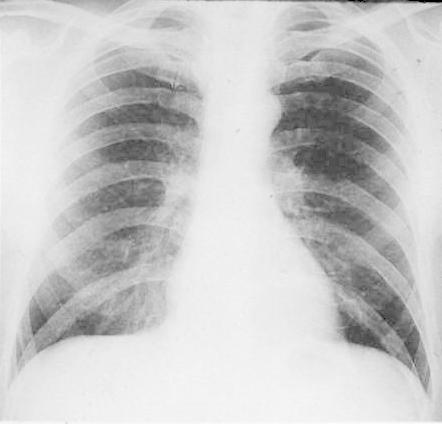

INSPIRATION

Poor Inspiration (picture to the right -->):

* False enlarged heart

* Difficult evaluation of the lungs

Same patient on inspiration (below):

|